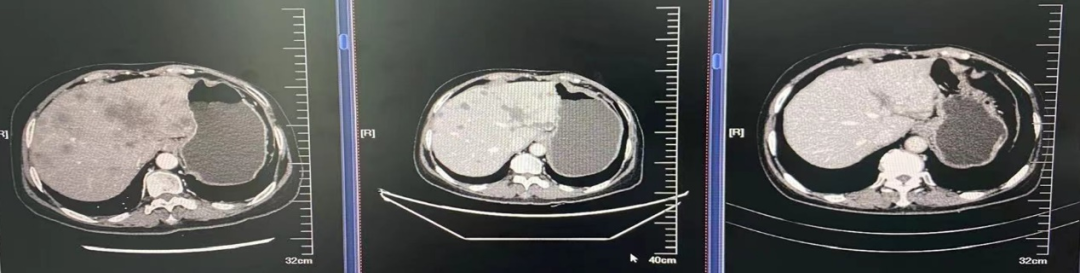

2021.04.05至荥阳市中医院查CT:1、左侧乳腺癌术后;2、双肺多发结节,转移可能,感染性病变待排;3、胸椎异常密度,转移可能;4、冠状动脉钙化;5、肝内多发低密度影。

2021.04.06至河南省肿瘤医院完善CT:双肺、肝、骨多发转移灶可能;ECT:全身多发骨质代谢异常,考虑多发骨转移。

2021年4月9日肝脏穿刺病理及免疫组化:ACK7(+)、CK19(+)、GATA-3(弱+)、SOX-11(-)、GCDFP-15(+)、Mammaglobin(弱+)、AFP(-)、Hepatocyte(-)、Arg(-)、CK5/6(-)、ER(<1%)、PR(-)、CerbB2(3+)、Ki-67(+15%)